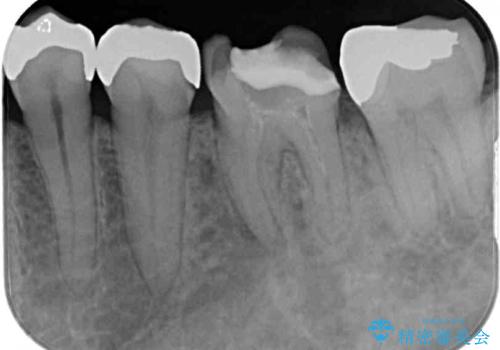

奥歯に痛みがあるとのことで診察を行ったところ、海外(アメリカ)にて処置をした手前の歯が既に失活していることが分かりました。なお、治療を行った大臼歯はレントゲン写真上の治癒が認められました。

症状のあった歯に対しても根管治療を行い、同様に補綴治療を行いました。